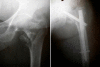

We report a randomised prospective study comparing two implants, the Gamma trochanteric nail and the ACE trochanteric nail, in the treatment of intertrochanteric femoral fractures in the elderly. One hundred and twelve patients were randomised on admission into two treatment groups. Fifty-six patients were treated with Gamma nail implants, and 56 were treated with ACE trochanteric nail. The average age of these patients was 78 years. Twenty fractures were stable and 92 unstable. The mean follow-up time was 8 months (6 -12). Regular clinical and radiological review was done 1, 3 and 6 months postoperatively. Operation time, fluoroscopy time, blood transfusion and complications were recorded. The mobility score was used to assess the pre-injury and postoperative mobility status. All the patients were treated within 36 h of their accident. There were no complications during surgery. All the patients were mobilised in the first 24 h postoperatively, regardless of the fracture type, and weight bearing was permitted as tolerated. Union of the fracture was achieved in all patients. There was no statistically significant difference between the two groups with regard to the studied parameters. There was no mechanical failure of the implants despite the early patient mobilisation. Early operation and early mobilisation resulted in a good functional outcome in all patients. Both the trochanteric gamma nail and ACE trochanteric nail provide effective methods of treatment for intertrochanteric fractures in elderly patients.